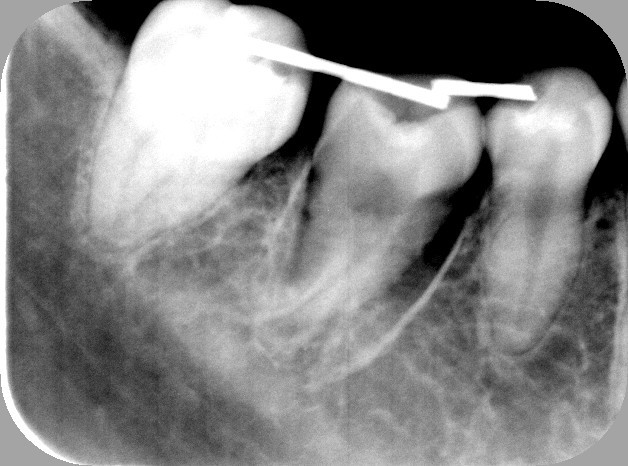

2.抜歯直後